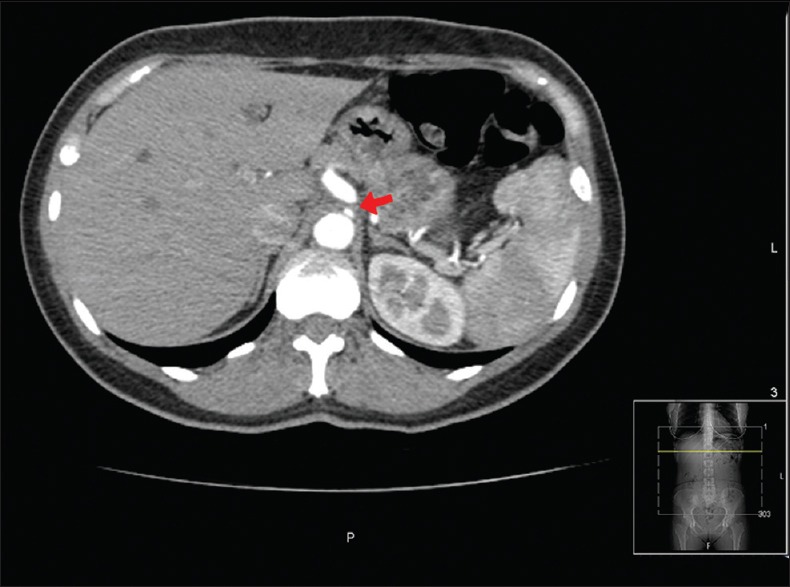

A 49-year-old woman with medical history of polymyalgia rheumatica presented with 3 weeks history of epigastric pain worse after meal. Gallstones, peptic ulcer, bowel ischemia, bowel obstruction, gastroesophageal reflux disease, chest pathology, etc., were excluded from the study. Computerized tomography showed a short stenotic segment at coeliac trunk with poststenotic dilatation of 8 mm. Ultrasound scan showed peak velocity of 326 cm/s at the coeliac artery. Diagnosis of median arcuate ligament syndrome was made.